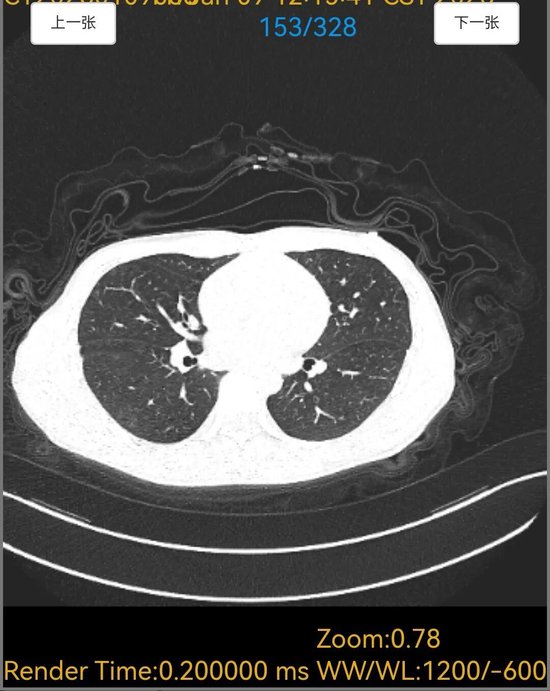

诊断明确后,呼吸内科医师团队制定了针对性极强的精准治疗方案。令人惊叹的疗效随之出现,在针对性药物治疗仅5天后,患者复查胸部CT。影像对比显示,原本遍布双肺的弥漫性“毛玻璃”阴影已基本完全吸收

从病因不明到转危为安,这场救治,彰显了平原县人民医院呼吸内科在重症肺部疾病诊疗中的过硬实力。